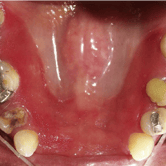

Edentulismo parcial

Pérdida de uno o más dientes en una arcada dental, afectando la masticación y la estética.

Esta condición puede llevar a la migración de dientes adyacentes y desalineaciones adicionales. También puede provocar una sobrecarga en los dientes restantes.

El edentulismo parcial puede afectar la calidad de vida del paciente al dificultar la alimentación y el habla.